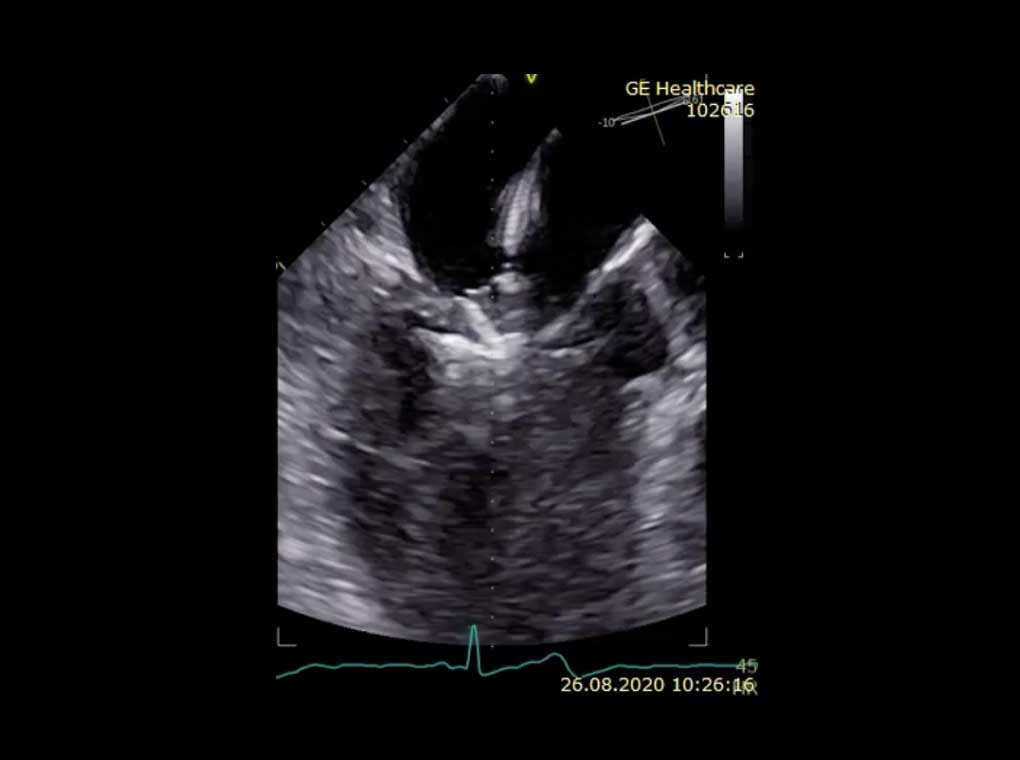

3D-TEE, Schluckechokardiographie

Flatterndes Segment des hinteren Segels (roter Pfeil) bei abgerissenen Sehenfäden und schwere Mitralklappenundichtichgkeit

3D-TEE Untersuchung einer schwer undichten Mitralklappe

Inkompletter Klappenschluss (roter Pfeil) bei stark erweiterter Herzkammer

Schwere sekundäre Mitralklappeninsuffizienz (-Undichtigkeit)

Schwere sekundäre Mitralklappeninsuffizienz (links) bei sonst unbeschädigter Mitralklappe (rechts)